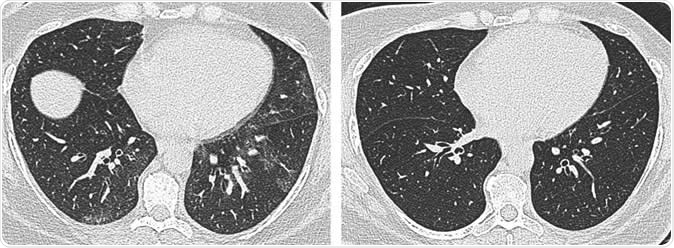

Axial unenhanced inspiratory CT images of the lungs in 51-year-old woman (a) before and (b) 6 months after bariatric surgery with 31-kg weight loss (body mass index decrease, 36.1%). The mosaic attenuation seen before surgery resolved after surgery.  Image Credit: Radiological Society of North America

When the team compared CT results before and after the weight loss surgery, they found that the surgery and the resulting weight loss were tied to structural and morphological changes in the lungs and trachea. There was reduced air trapping, which is a strong predictor of improvement in breathing issues or difficulty of breathing, and lower incidence of tracheal collapse.